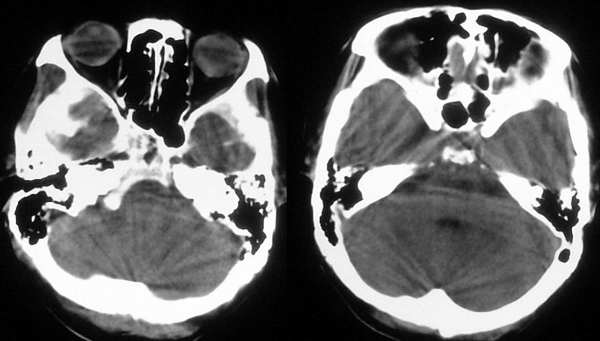

患者,女,45岁,头痛、头昏一周。(左侧内囊膝部、左侧内囊前角旁区域点状稍高密度影形成原因,请分析)

jiajie斑主已经对图象做了标识,左侧苍白球部位的高密度影可以考虑为苍白球的钙化,苍白球钙化可以单侧分布,只不过很少罢了,当然也很有可能是组织重叠造成的假象。左侧侧脑室前角旁的高密度影为假象,象素构成的黑白图象难免会有几个密度相近的几个象素相邻,其实正如jiajie斑主所示,仔细观察还能找到很多点片状高密度影,其中相当部分是由伪影构成。另外“病变”周围没有水肿和占位效应,结合患者临床表现应该为正常表现。l-y~t~001提出胶质增生的可能,胶质增生在ct上往往为低密度,本例不符合。

1、这个部位特殊:左侧内囊的膝部及后肢的前部,这个部位如果有病变,会有明显的皮质脊髓束的神经症状,而本病例没有;

2、正如前面多数人所说,“异影”周围没有水肿影像,也没有占位效应;

3、“异影”密度不高,略高于脑白质,与灰质相近;

4、仅仅一个层面,而上下层面没有;

归纳----以上所述不符合病理性的影像学改变。

解释----1、部分容积效应;2、伪影。

建议----ct薄层扫描(扫描前做水模校正);mr检查。